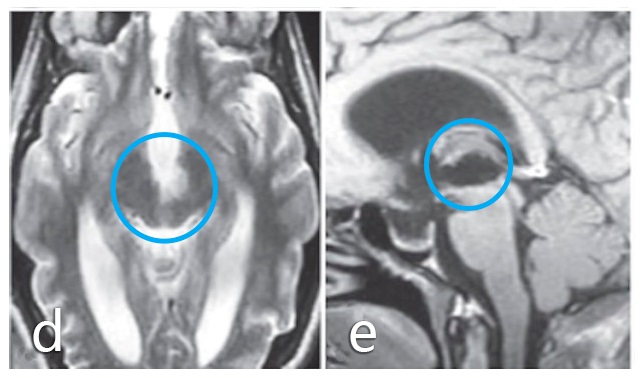

术前:a、b图患者术前MRI显示中脑肿瘤,患者初期接受立体定向囊肿抽吸和间质放疗,并被诊断为毛细胞型星形细胞瘤,但肿瘤仍在生长。

手术入路和体位:病人仰卧位(c图),通过左侧颞下入路进行手术。事先放置腰部引流管,并在暴露期间释放脑脊液以放松大脑并避免颞叶损伤。术中完整保留Labbé静脉(d图),通过切开其周围的蛛网膜层而与颞叶分离。e图表示使用小型Cavitron超声手术抽吸器(CUSA)探针切除肿瘤,同时保护邻近的滑车神经(箭头指示)。

术后:无手术并发症,f图显示伤口愈合正常,患者预后良好,无神经功能缺损。组织病理学检查为1级毛细胞型星形细胞瘤。g、h图术后MRI影像显示,肿瘤全切。随访MRI记录手术后9年无肿瘤复发。